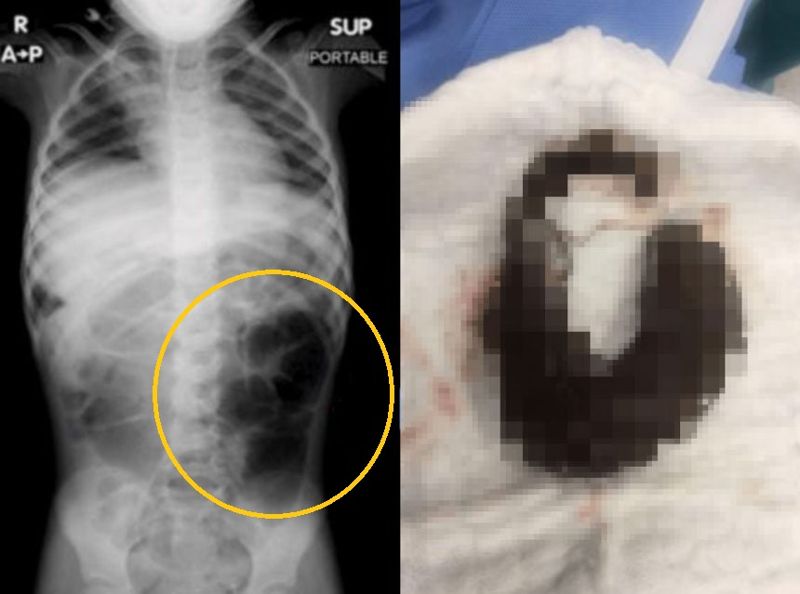

22일 큐레우스 저널에 따르면 사우디아라비아에서 6세 여아가 복통과 지속적인 소화 불량을 호소해 검사를 받은 결과 위장 내 큰 이물질이 발견됐다.

수술 결과 위에서 나온 이물질의 정체는 바로 머리카락 덩어리였다.머리카락 덩어리는 위에서 소장까지 길게 이어진 모습이었다.

복부 진찰,대변 검사,영상 검사(CT,소셜카지노 pdfX레이)를 통해 진단한다.아동·청소년의 심리적 불안정이나 스트레스 해소 목적으로 나타나 정신과적 치료가 병행된다.수술은 위와 소장까지 이어진 모발석을 제거하는 방식으로 진행된다.